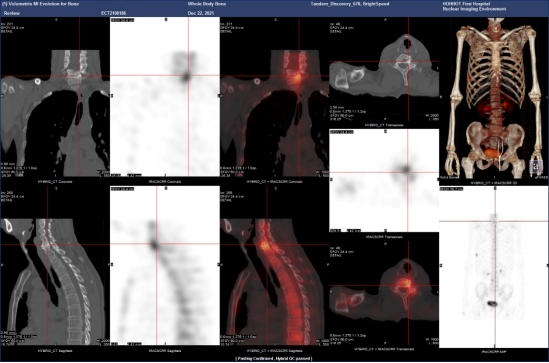

(病例三)患者,男 44岁,左肺下叶恶性肿瘤(T4N2M1c,IVB),纵膈继发性恶性肿瘤,胸膜继发性恶性肿瘤,骨和骨髓继发性恶性肿瘤。靶向药物治疗后为评估骨继发恶性肿瘤来诊。MIP图示:与2021-8-3日片比,2021-12-21日片示左侧第8后肋病灶放射性摄取明显减低,左侧第3后肋、胸骨柄片状放射性摄取范围减小,右侧第6前肋、L2椎体放射性摄取范围无明显变化。结论:与2021-8-3日片比:左侧第8后肋、左侧第3后肋、胸骨柄病灶骨盐代谢明显减低,提示肿瘤细胞活性减低;右侧第6前肋、L2椎体病灶骨盐代谢无明显变化。